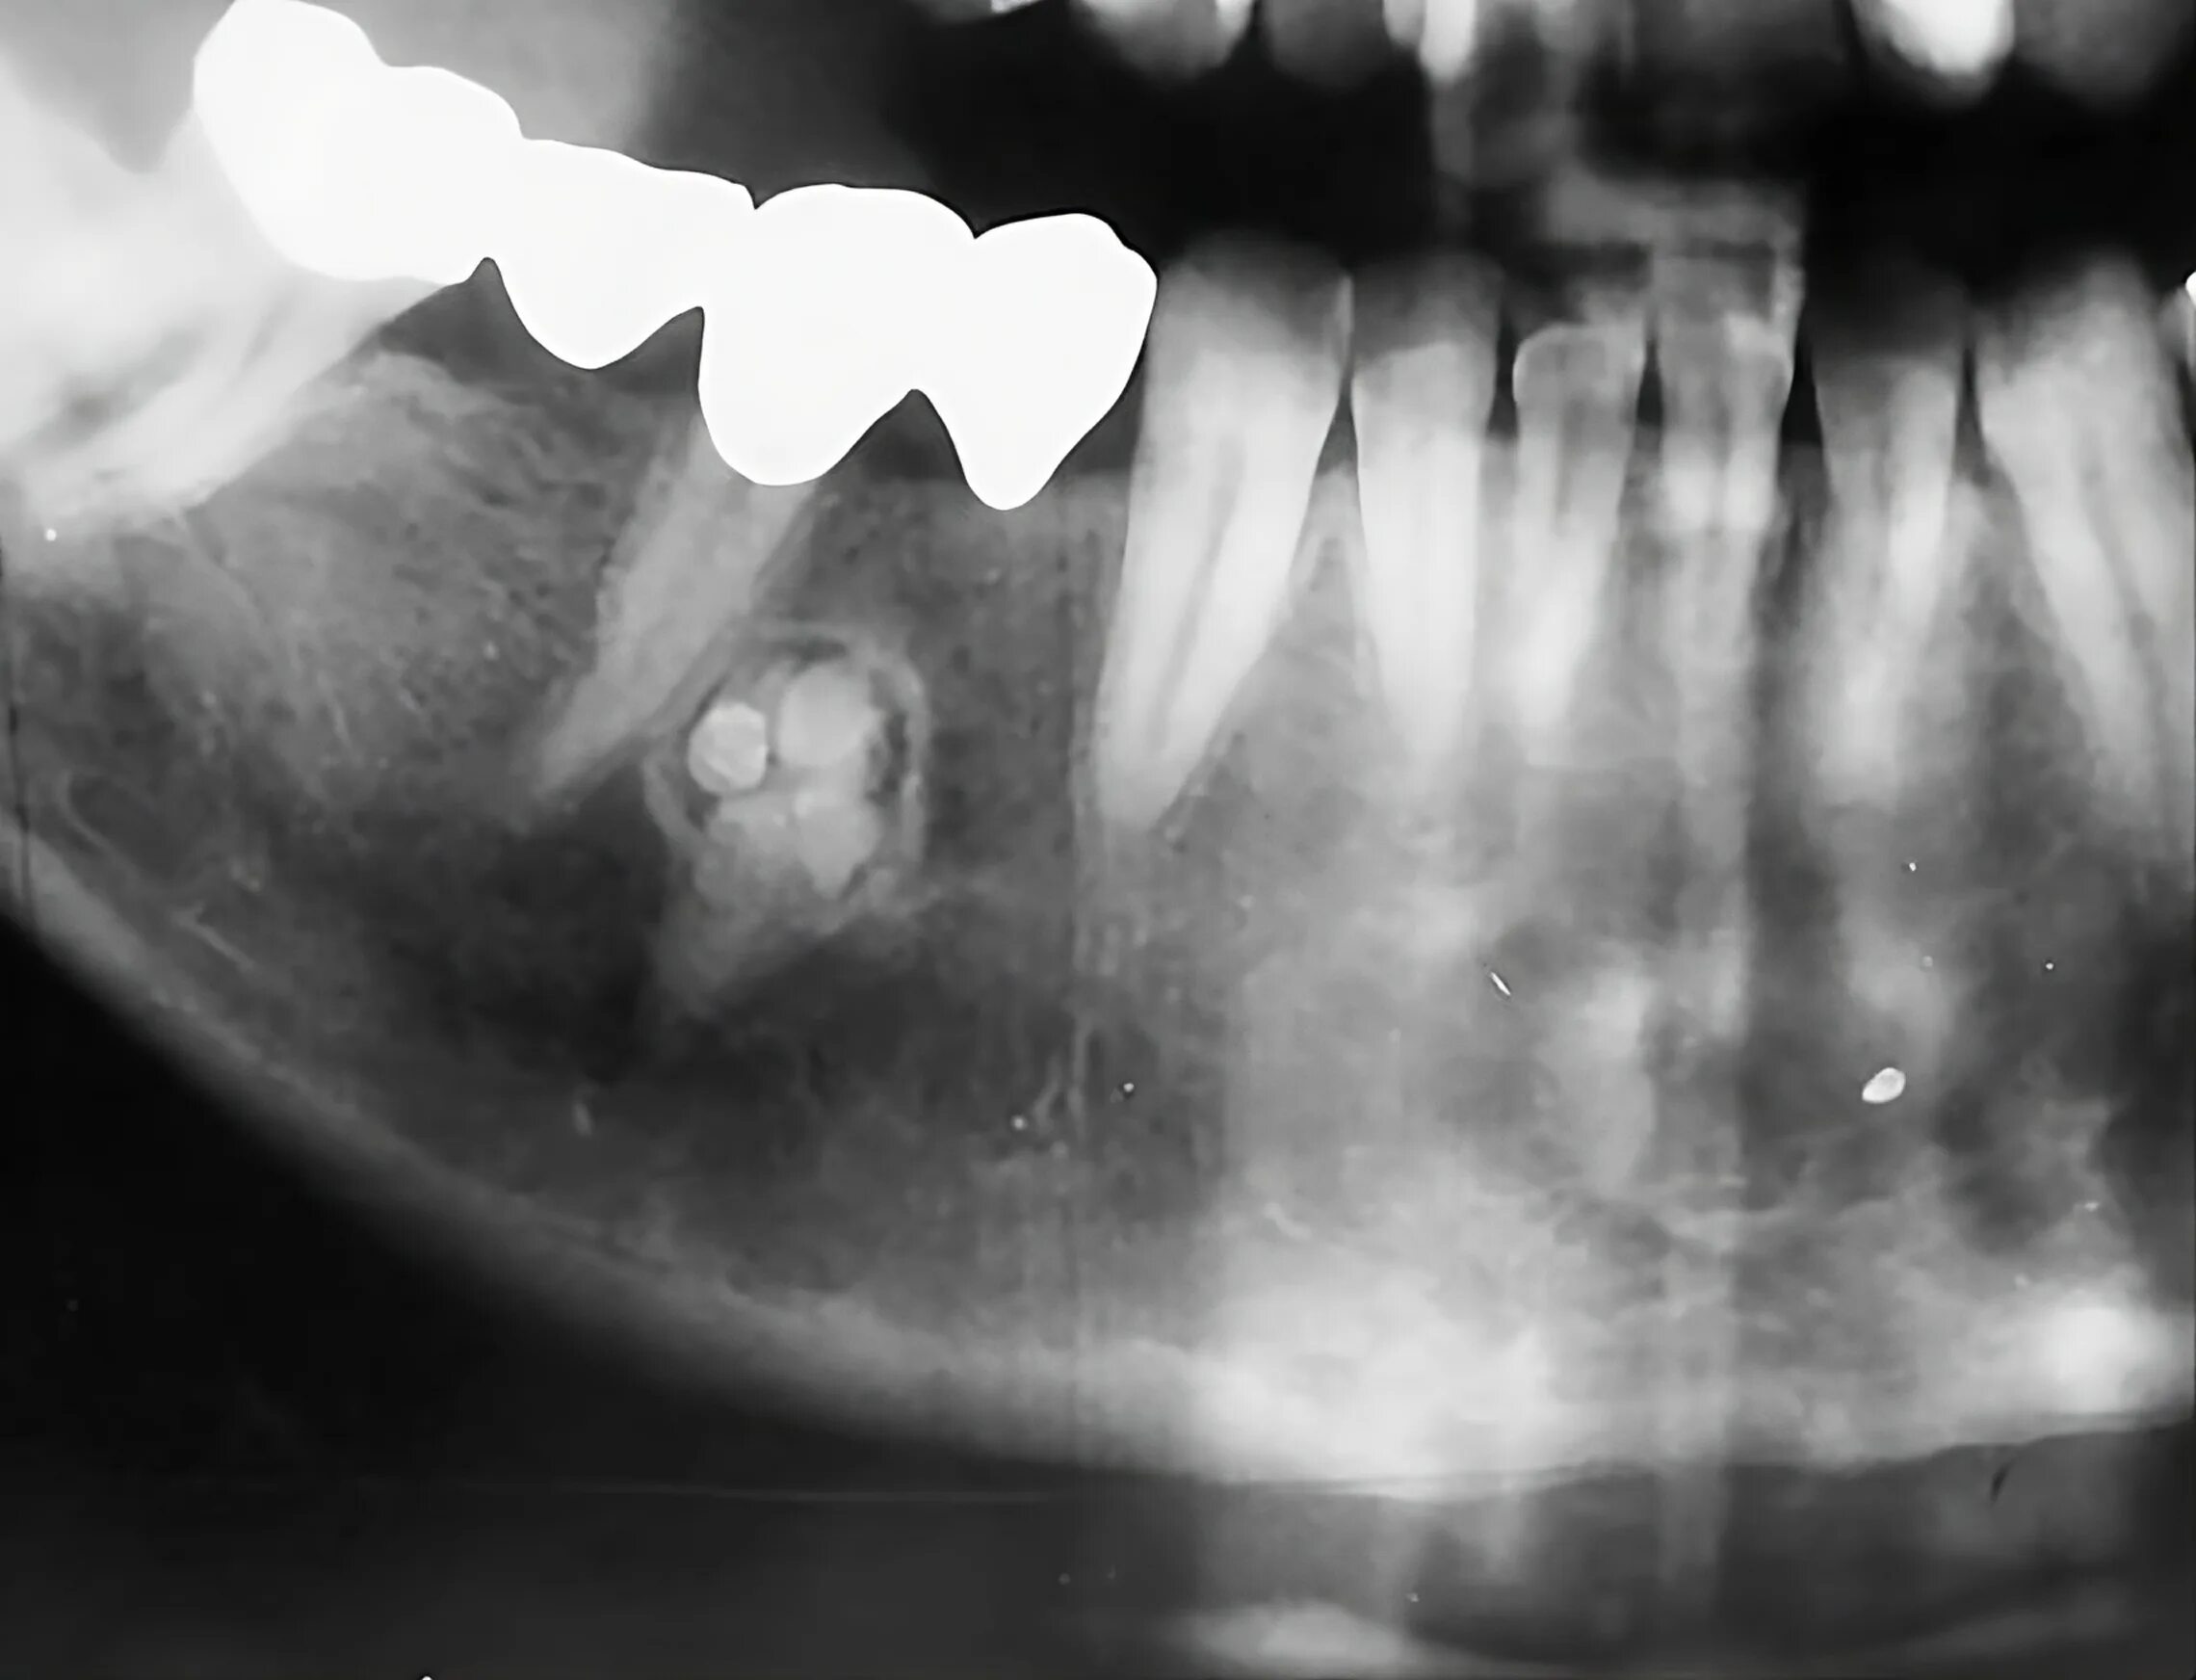

Снимок ротовой полости